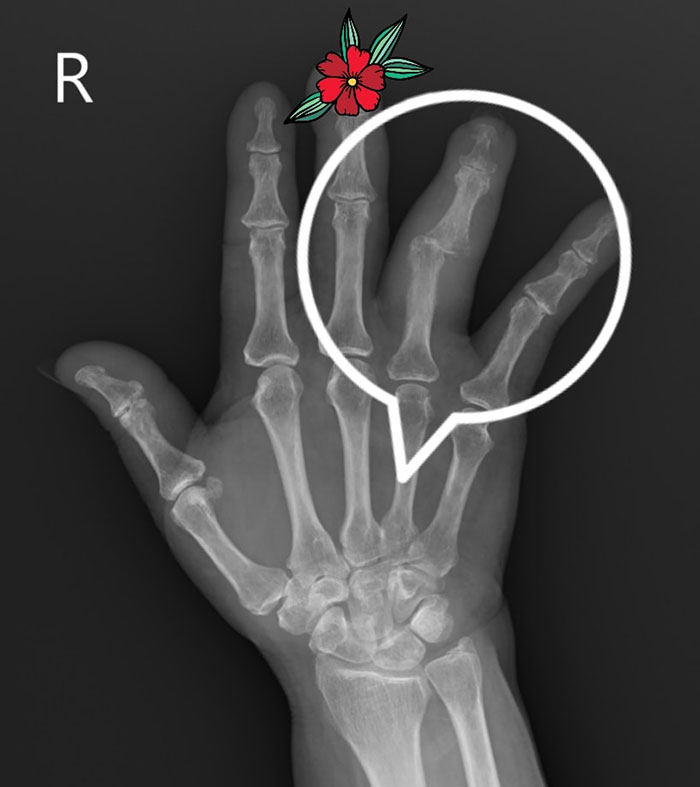

ต่อมาเห็นว่านิ้วบวมผิดรูปไปมากจนงอนิ้วไม่ได้ อยู่เฉย ๆ ก็ปวด อากาศเย็นตอนเช้า ๆ จะปวดมาก กินยาพาราเซตามอล ยาต้านการอักเสบ พอบรรเทาลงได้บ้าง แต่ไม่ดีขึ้น จึงลองมาโรงพยาบาลสิชล ตรวจพบว่านิ้วนางข้างขวาบวมผิดรูปตั้งแต่โคนนิ้วจนถึงปลายนิ้วเป็นรูปกระสวย แพทย์จึงได้เจาะเลือดตรวจหาความผิดปกติของโรคข้อ เอกซเรย์กระดูกที่มือและทรวงอก พบว่าเห็นรอยโรคที่กระดูกส่วนที่บวมผุกร่อน ค่าอีเอสอาร์สูงกว่า 50 ผลเลือดอื่น ๆ ปกติ

เบื้องต้นจึงสงสัยว่าน่าจะเป็นเนื้องอกที่กระดูก จึงส่งต่อไปรักษากับแพทย์ผู้เชี่ยวชาญด้านกระดูก แพทย์ได้ทำการเจาะเอาเนื้อเยื่อไปตรวจ ผลยืนยันออกมาเป็นเชื้อวัณโรคในกระดูกนิ้วมือ ซึ่งพบได้น้อยมาก ๆ ร้อยละ 1 ของคนไข้วัณโรคเท่านั้น ส่วนใหญ่จะเป็นที่กระดูกสันหลัง หรือข้อสะโพก แม้จะพยายามค้นหาว่าเชื้อมาโผล่ที่นิ้วมือได้อย่างไรก็ไม่พบ